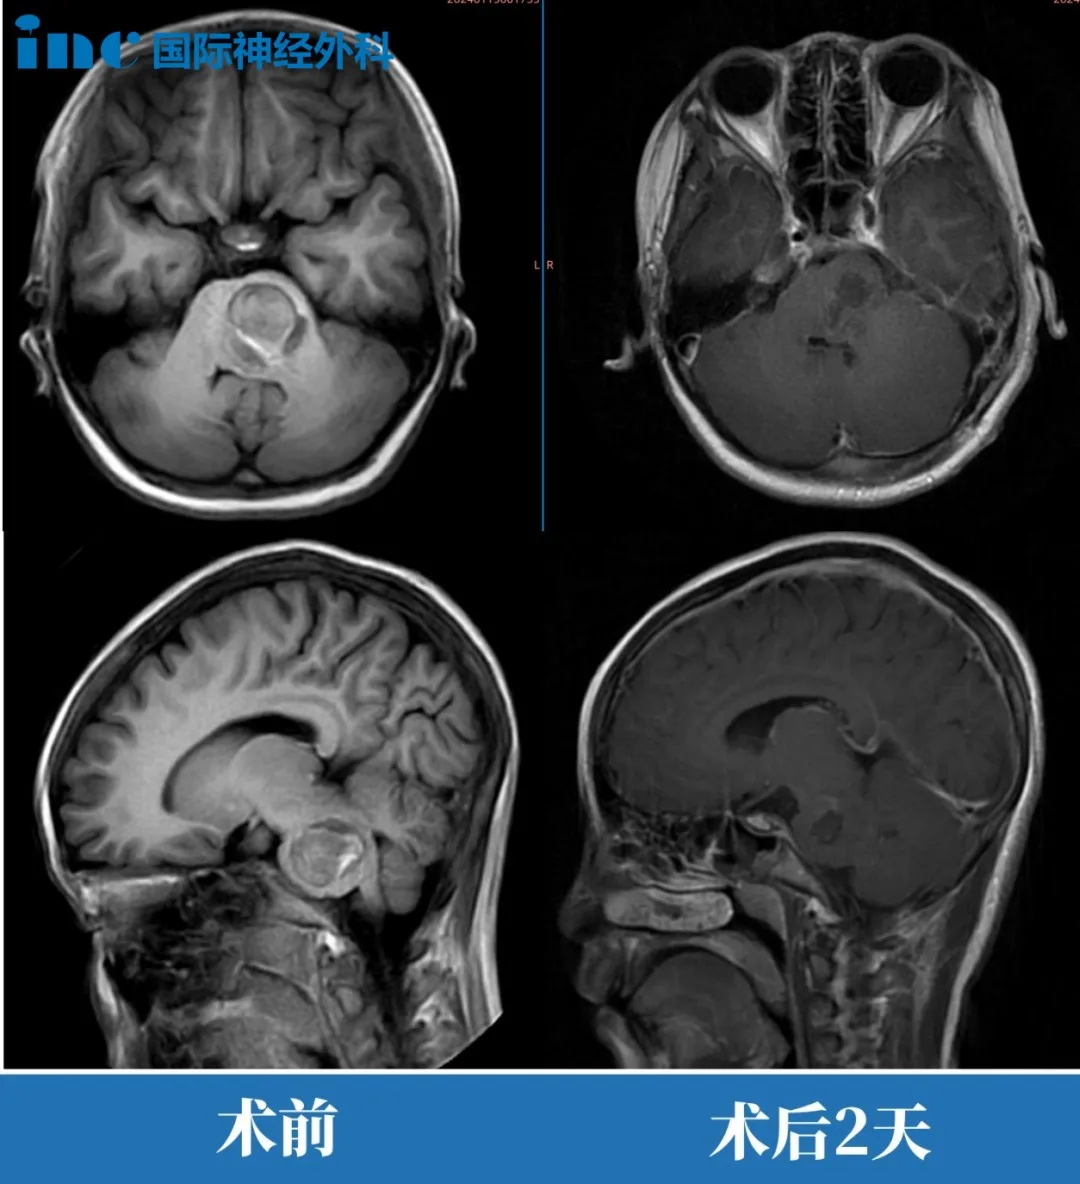

术前:脑桥占位。双眼斜视、畏光,面瘫,频发不自主扭头动作,走路稍有不稳。头颅MR(红色区域)显示:脑桥血肿,可见16 x 22 x 21mm肿块,四脑室受压变窄。

术后:头颅MR(蓝色区域)显示小脑半球及脑干形态正常,中线结构居中,原脑桥内团块状信号消失。